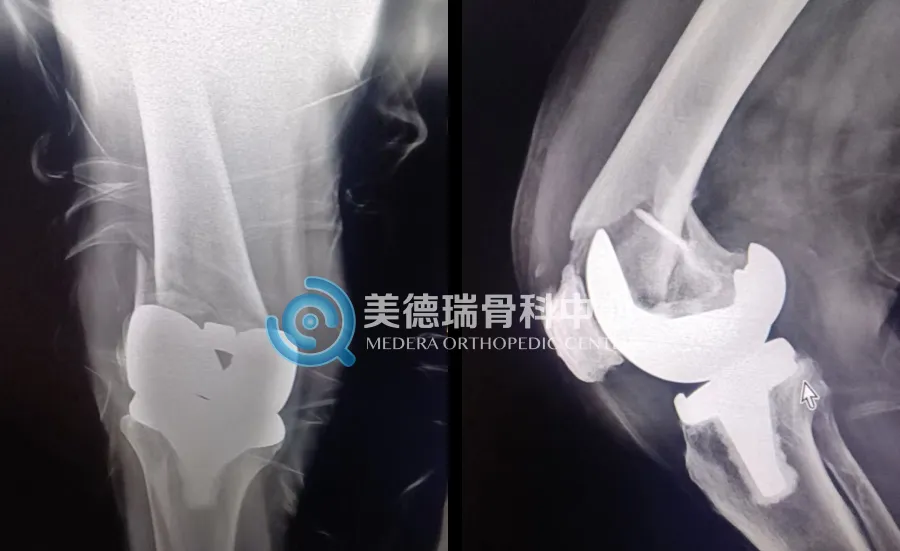

此次接受治疗的患者,在一年前曾进行右膝关节置换术。近期,因意外不慎摔倒,右膝直接着地,当即出现剧烈疼痛,无法站立,膝部甚至发出“骨裂”的声音。经当地医院检查,确诊为右膝关节置换术后假体周围骨折,随后被紧急送入北京美德瑞邯郸骨科中心。

手术当天,石晶磊医生带领手术小组为患者实施手术。术中,专家团队发现,患者骨折远端骨量足以支撑双钢板内固定。团队果断选择双钢板的内固定术,既保证了骨折复位固定后的稳定性,又能减少手术创伤和手术时间,对高龄患者尤为重要。